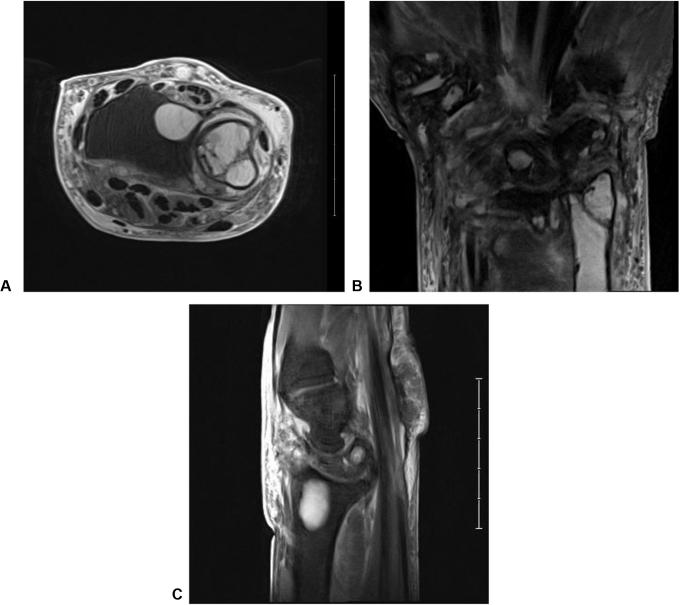

骨内肿瘤性二水焦磷酸钙晶体沉积病诱发的罕见病理性尺骨骨折

An Unusual Pathologic Ulna Fracture Induced by Intraosseous Tumoral Calcium Pyrophosphate Dihydrate Crystal Deposition Disease.

In this case report, we describe a novel occurrence of tumoral calcium pyrophosphate dihydrate crystal deposition disease (TCPPDCD) in a 76-year-old man that presented as an unusual, intraosseous, metadiaphyseal lesion of a long bone causing a pathologic fracture. A routine intralesional biopsy was performed, demonstrating granular deposits composed of polarizing, overlapping rhomboid crystals consistent with TCPPDCD. With limited numbers of reported cases of TCPPDCD, and the atypical intraosseous origin seen in this case, it is paramount to thoroughly evaluate all cases of TCPPDCD to clearly differentiate key findings that are essential in diagnosing and managing TCPPDCD.

在本病例报告中,我们描述了一名76岁男性发生的新型肿瘤性焦磷酸钙二水合物晶体沉积病(TCPPDCD),其表现为长骨骨干中段不寻常的骨内病变,导致病理性骨折。进行了常规的病变内活检,显示出由偏振、重叠的菱形晶体组成的颗粒状沉积物,与TCPPDCD一致。鉴于TCPPDCD的报告病例数量有限,且本病例中出现非典型的骨内起源,对所有TCPPDCD病例进行全面评估以明确区分诊断和管理TCPPDCD所需的关键发现至关重要。